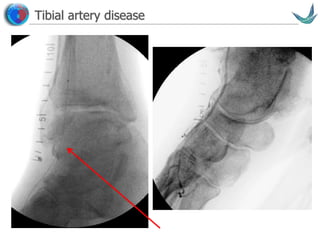

Tibial artery disease